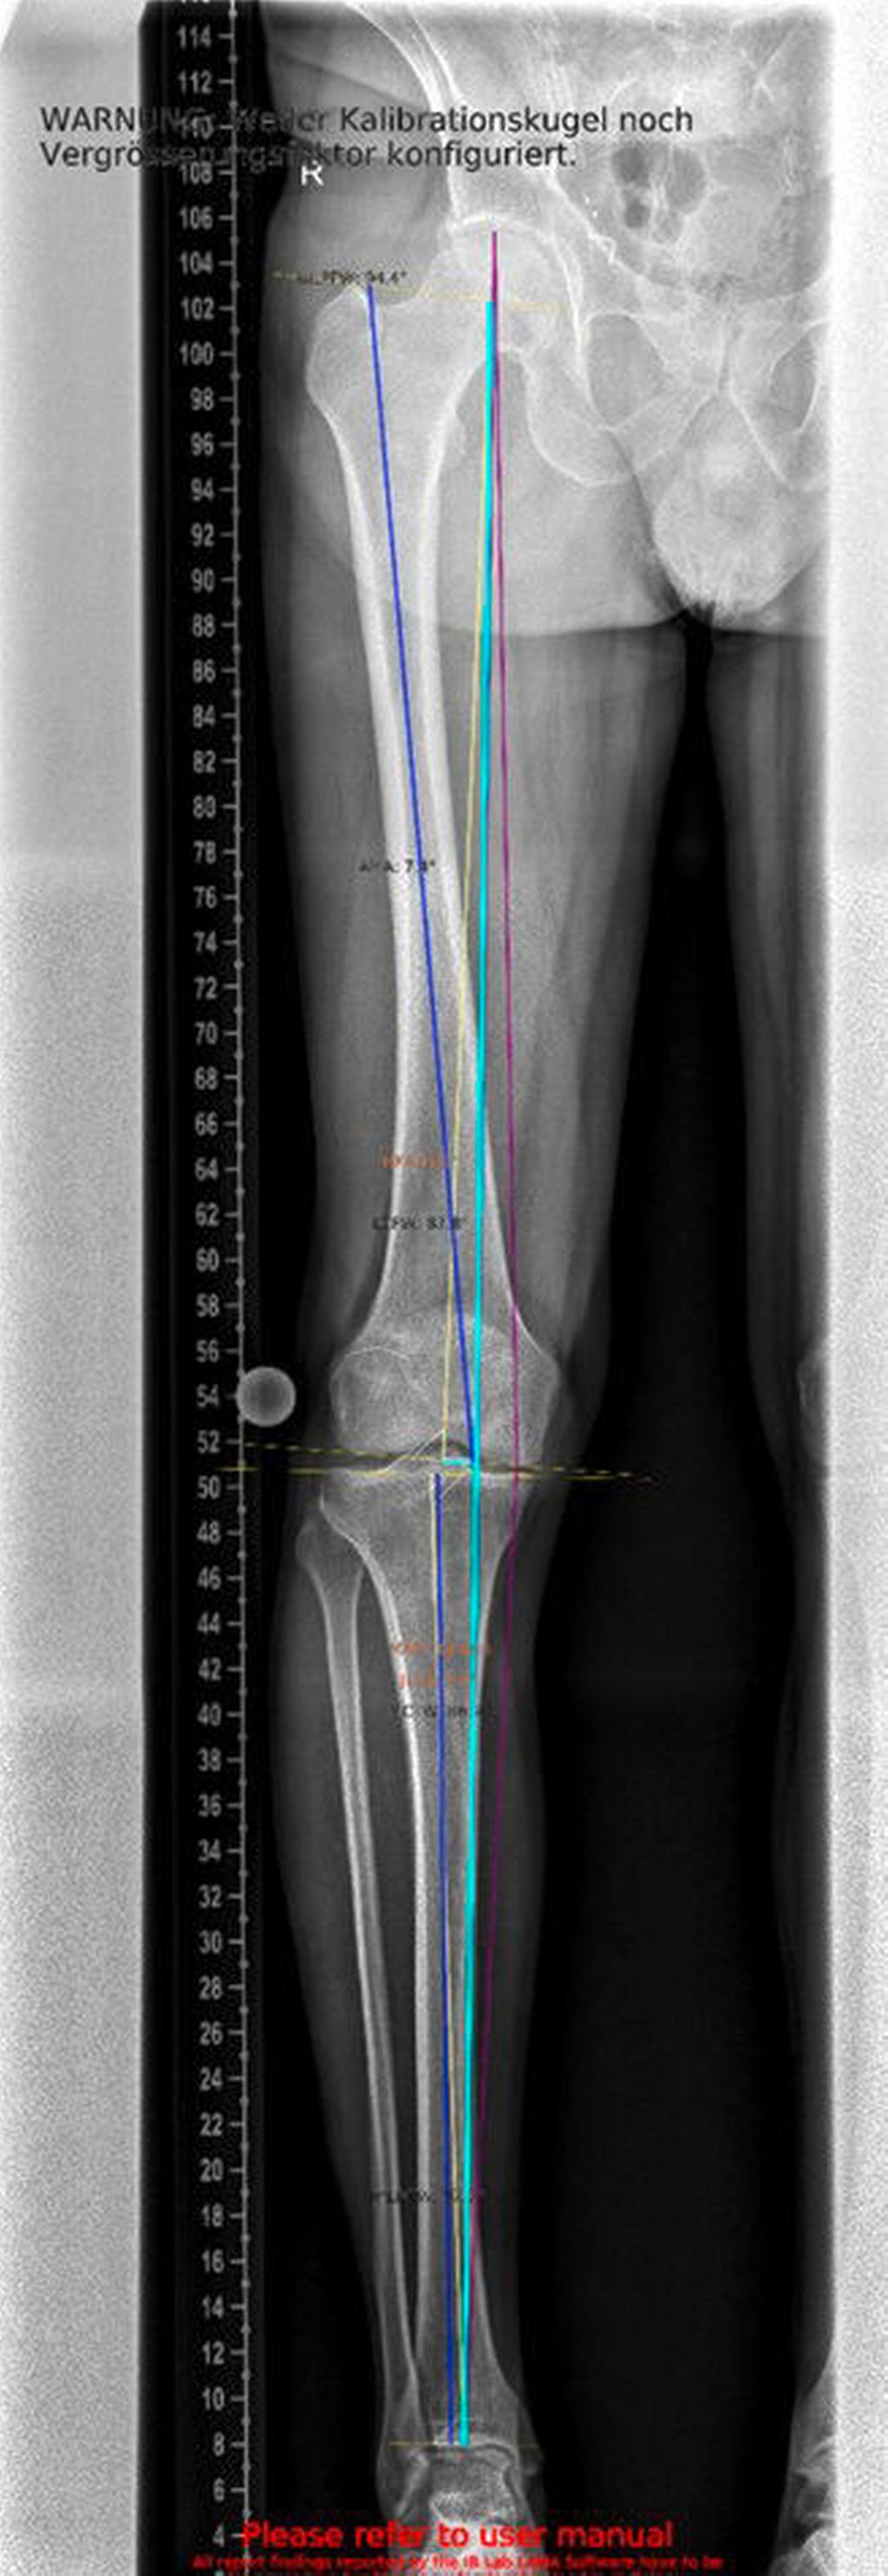

Relevanz der Beinachse bei der Therapie von degenerativen Meniskusläsionen